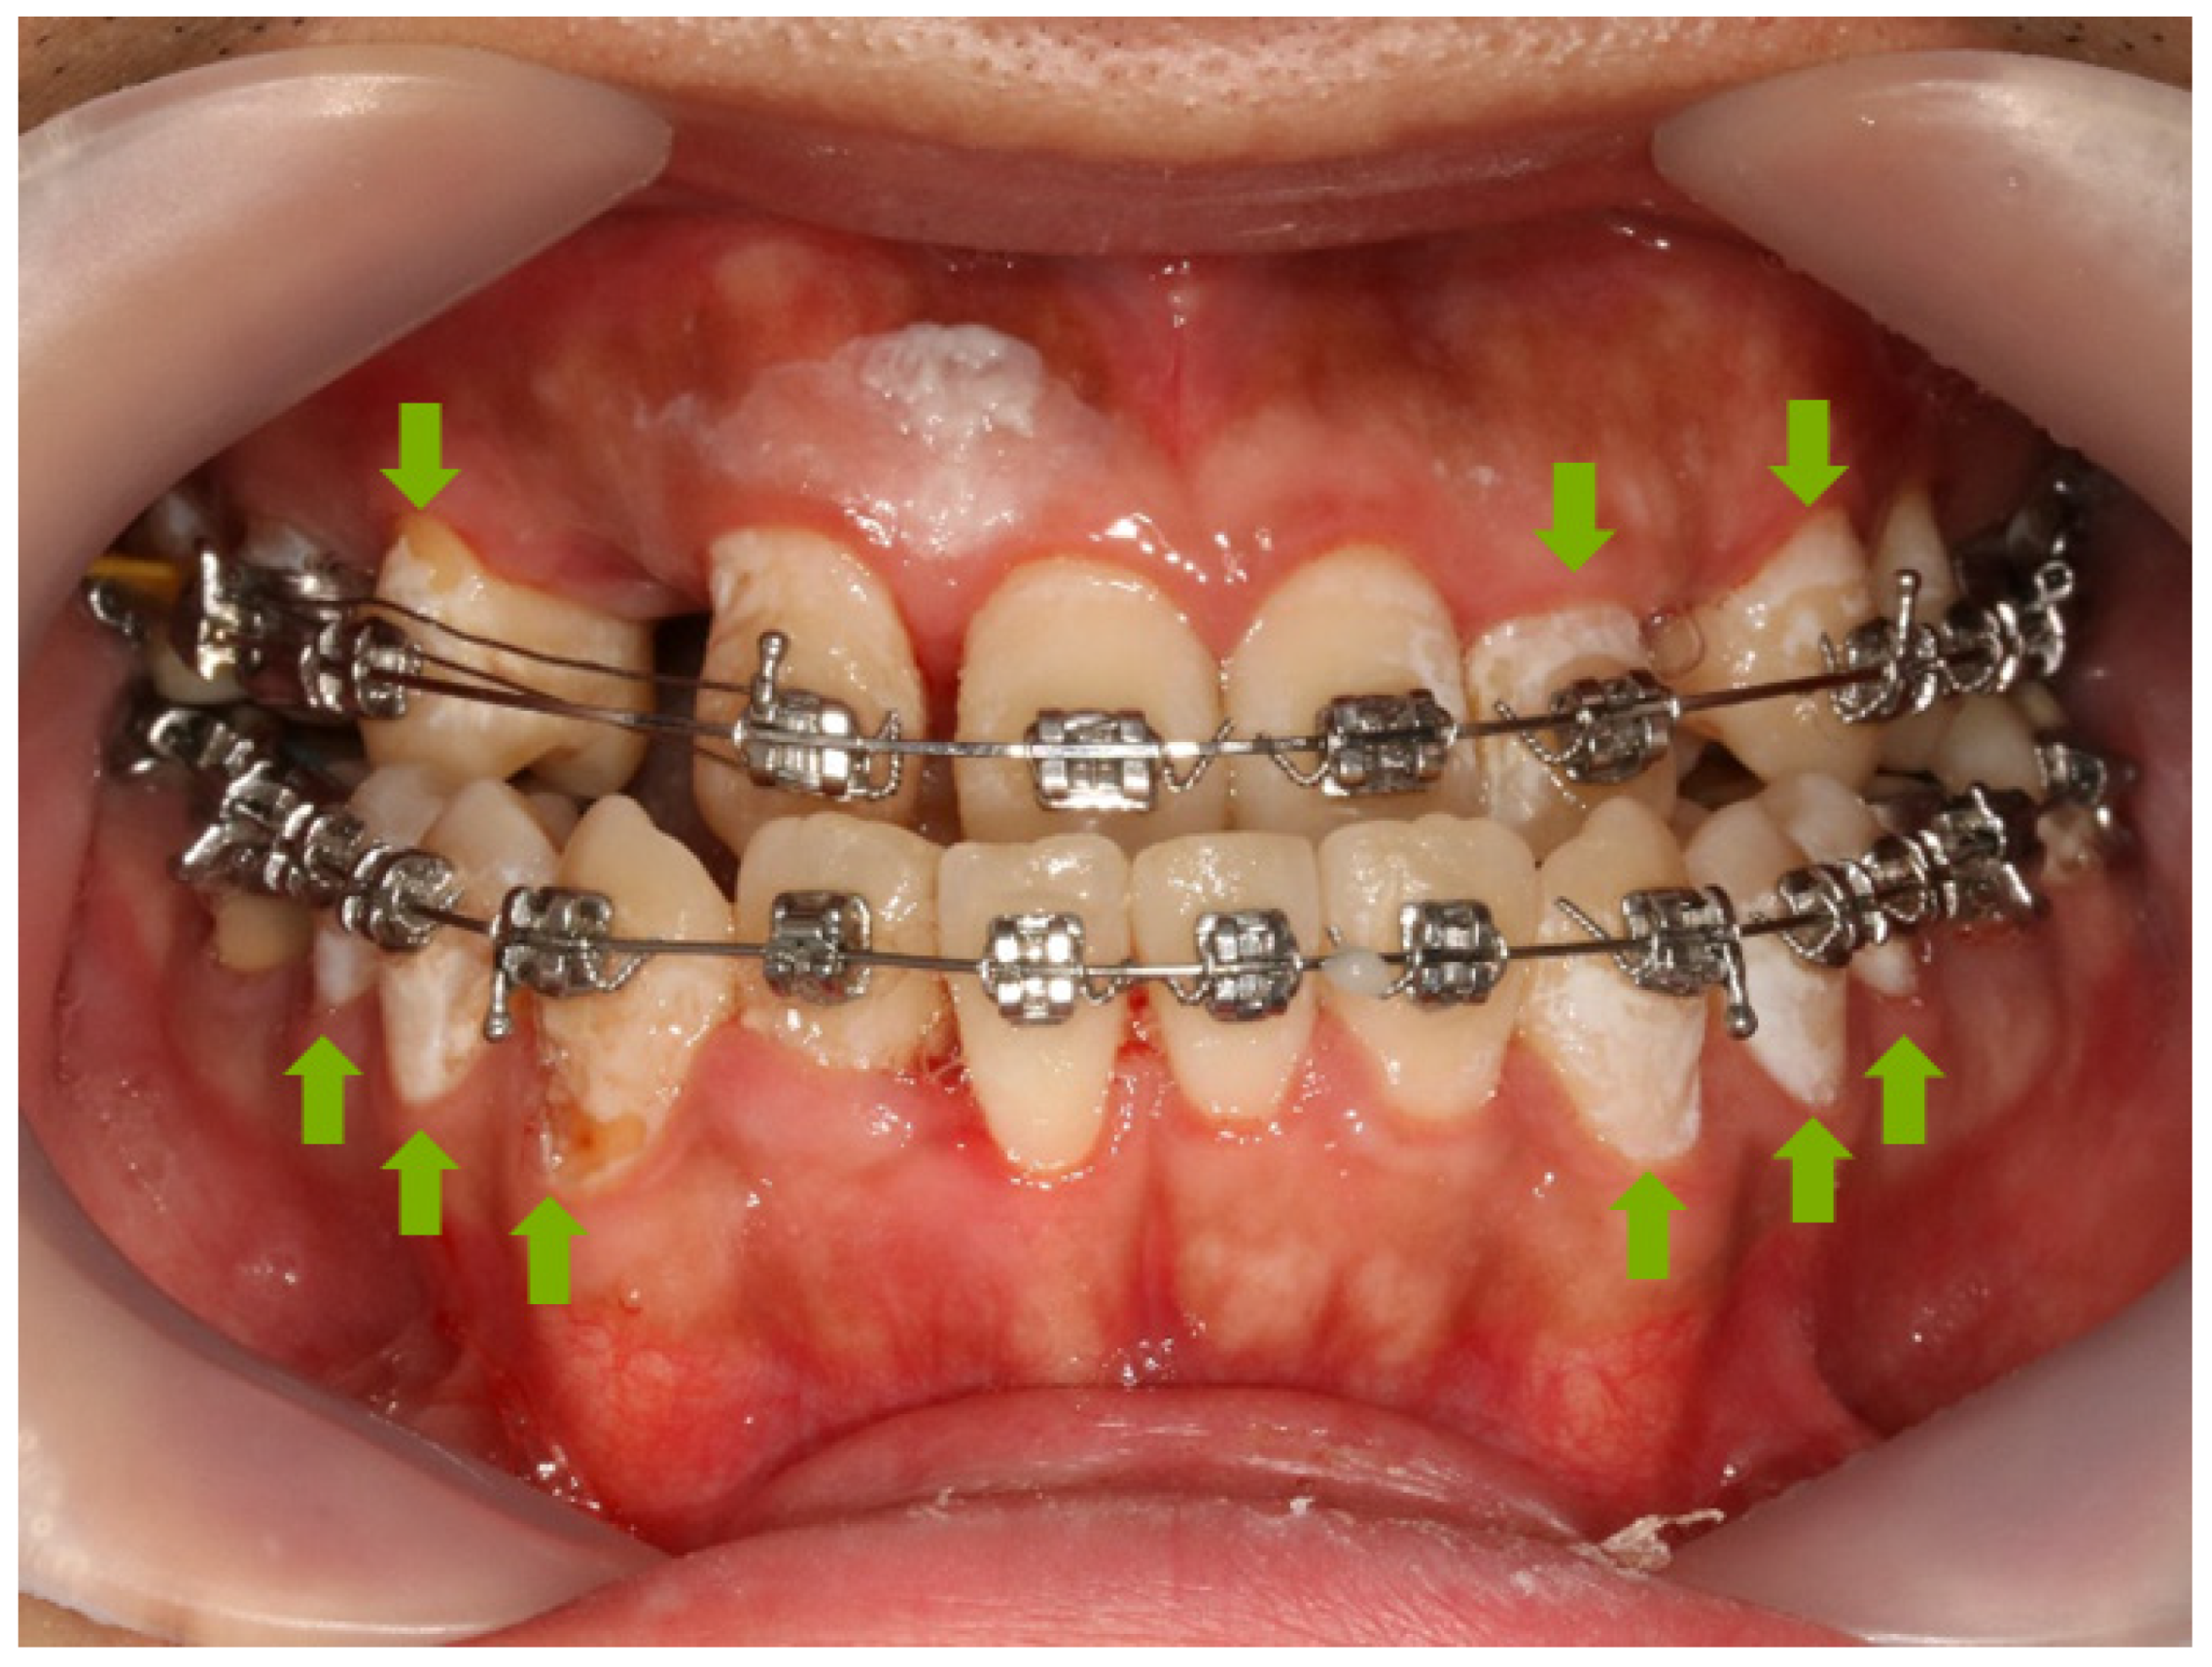

1. Introduction

3.8. Anti-demineralization

4. Discussion